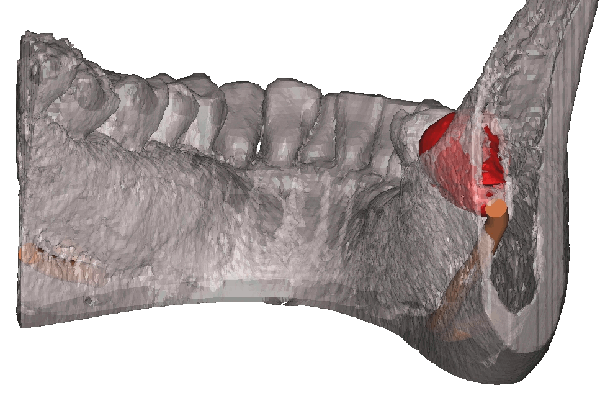

歯科用CTをもちいた歯の内部構造(根管の形態)の検査

歯科用CTを使用することで、レントゲン写真では確認できなかった病変をより正確に把握することができます。

2次元撮影では把握できない箇所も多くありましたが、3次元撮影によって確実性の高い治療を行うことができます。

シンプラント プロのコンピューターガイデッド インプラント治療では、歯科CT画像から3D画像を構築し、骨の厚みや神経の走行などを視覚的に診査できます。

そして嚙み合わせ、骨の厚みや神経の走行からからみて三次元的に理想的なインプラントの位置を画像上でシミュレーションすることができます。これにより手術を行う前に安全で理想的なインプラントの位置を決定することが可能になりました。

歯科CTデータからシンプラントで3D画像を表示して骨の厚みや神経、血管の走行を検査します

噛み合わせ、骨の厚みや神経の走行からみて理想的なインプラントの位置を決定